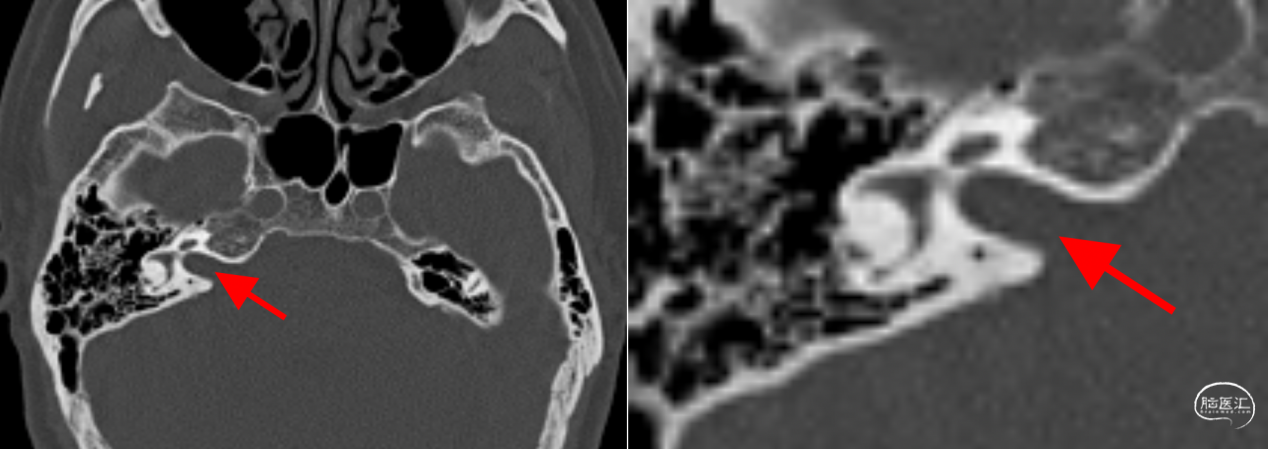

术前颞骨CT:右侧内听道未扩大。

颞骨CT,内听道后壁无明显气化,无高位颈静脉球,可安全磨除内听道后壁。患者术前右耳听力AAO-HNS分级A级。

术后颞骨CT显示内听道后壁磨除范围。